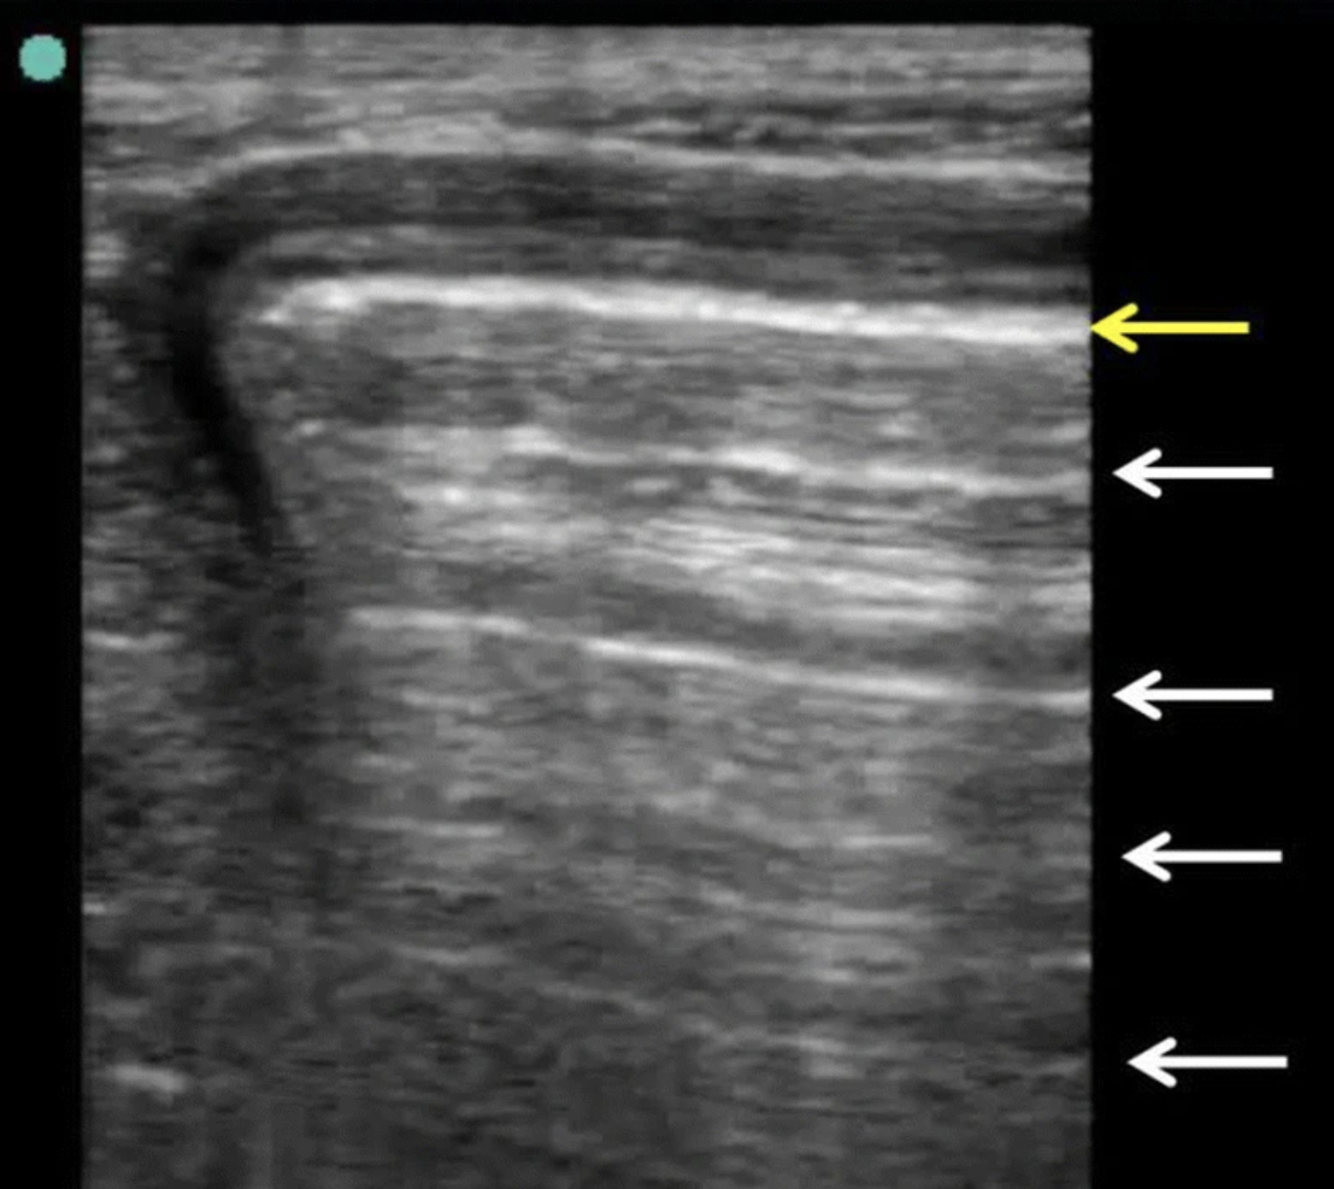

Name this artifact.

What is the cause of the artifact?

Reverberation: Occurs at highly reflective surfaces (e.g., tissue-gas interface). Some echoes are reflected back and forth between gas and transducer, then interpreted to exist at twice the depth of the original interface.